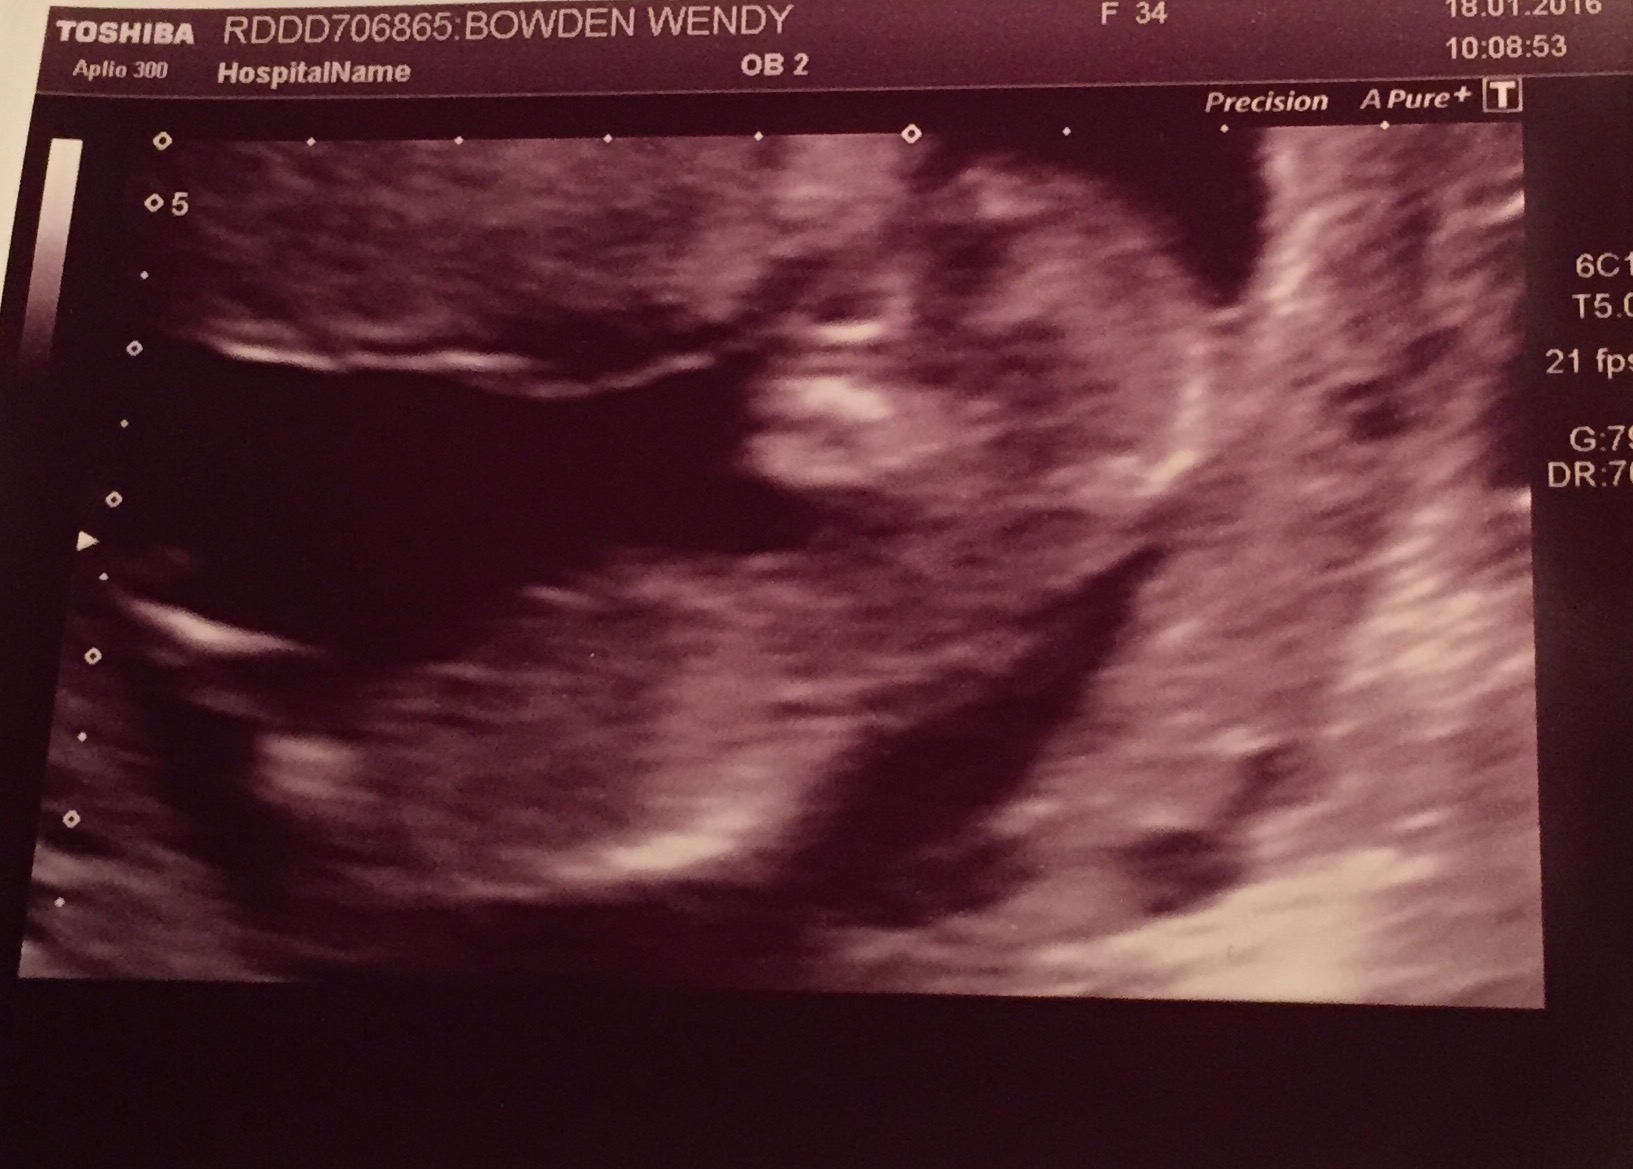

Would you say this is a girl? I can see 2 white lines?Attachment 30563

It could be a girl but it looks quite angled. Baby's bum is in the air which makes it hard to read. Slight girl lean from me.

according to nub theory , the angle is less than 30 degree for this baby. I think it a girl.

This scan was at 13 weeks.